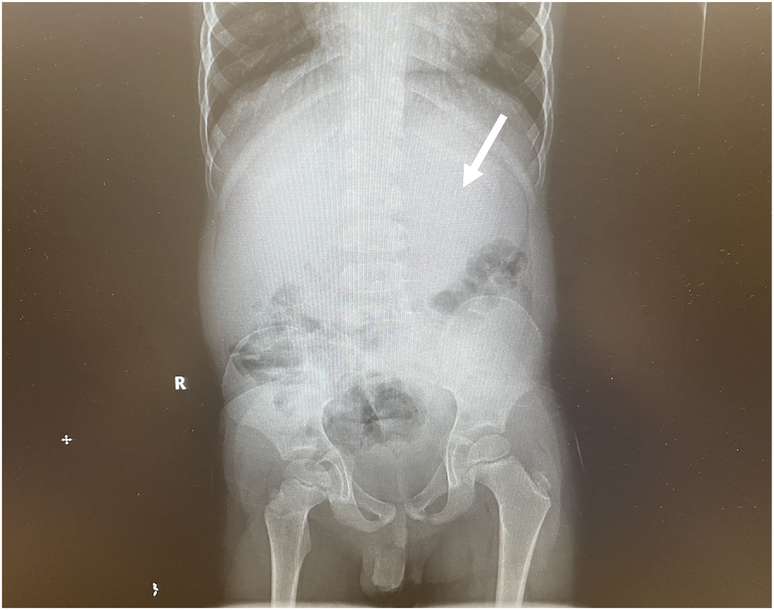

Os exames do garoto de Ohio revelaram que ele tinha um grande acúmulo de bezoar ocupando 25% do seu estômago. A solução foi puxar parte por parte da massa de volta pela garganta e pelas passagens do esôfago (canal que conduz o alimento até o estômago).

O menino precisou permanecer deitado de costas com um esofagoscópio, tubo de metal oco, posicionado em sua garganta. Em "várias passadas" e com auxílio de outros instrumentos, como pinças, os pedaços foram removidos pela equipe médica, que divulgou o caso na JEM Reports no início de maio.